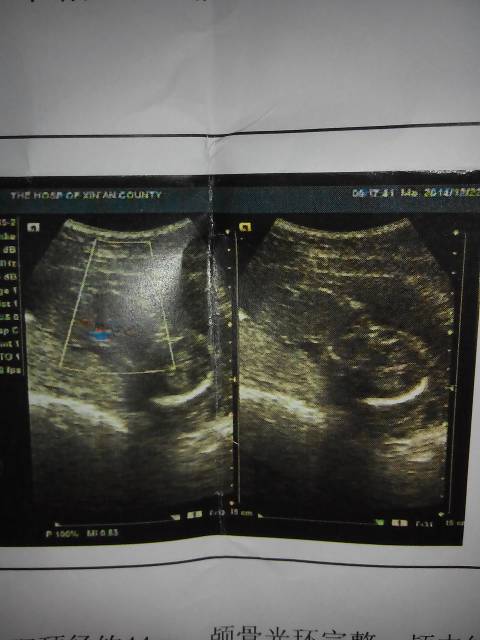

麻烦懂得帮我看看,这胎儿有手脚么 点击展开 玮晨妈妈 2014-12-25 08:47 为您推荐: 其他回答 你好,从图片上不能看出,不能通过动态B超检查宝宝发育情况是否正常。 张笑珠 2014-12-25 09:20 相关问题 做四维彩超30周4天宝宝手脚偏短3周,麻烦你帮我看看正常吗?非常感谢! 昨天去医院做四维 医生什么都没说 就说还好 我感觉那个医生不专业 麻烦懂得帮我看看 孕妇肚皮痒,长了很多红点,有图,麻烦懂得帮我看看是什么